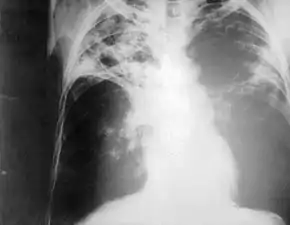

![]() Chest radiography showing advanced bilateral pulmonary tuberculosis. Source: CDC | |